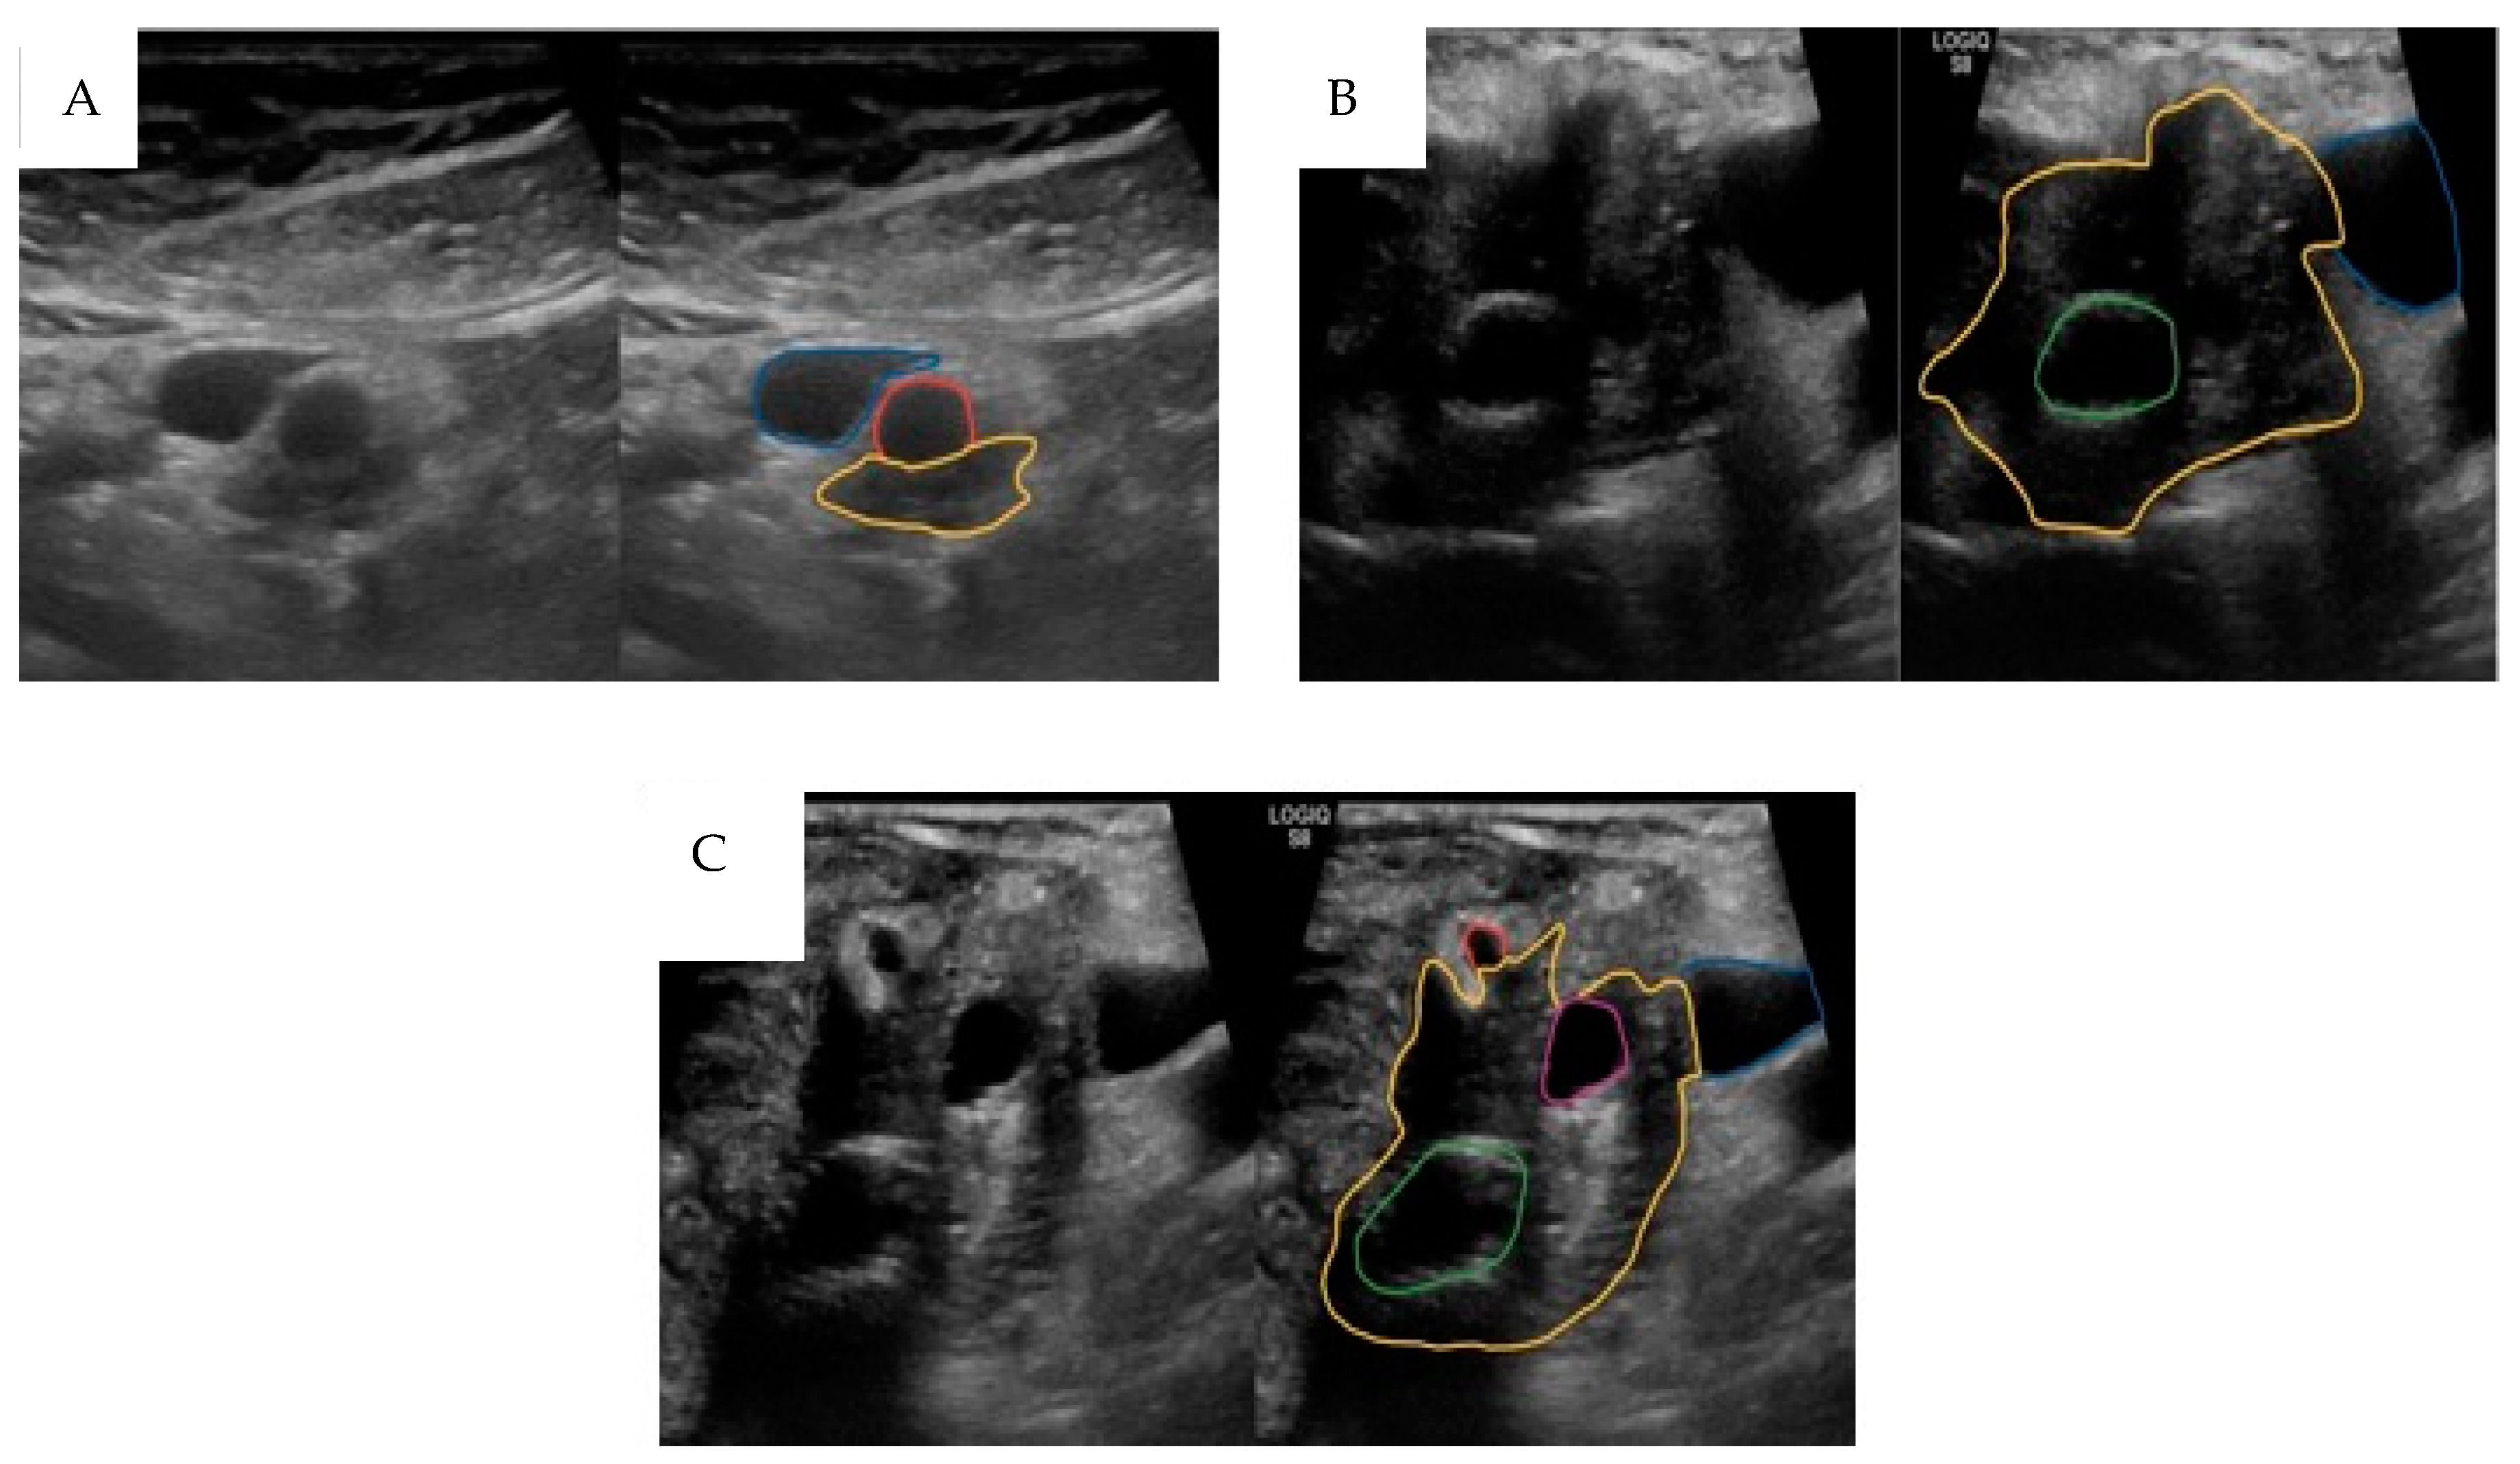

3.2.2. Intra-Operative Ultrasound (IOUS)

- Michiels, N.; Doppenberg, D.; Groen, J.V.; van Veldhuisen, E.; Bonsing, B.A.; Busch, O.R.; Crobach, A.S.L.P.; van Delden, O.M.; van Dieren, S.; Farina, A.; et al. Intraoperative Ultrasound During Surgical Exploration in Patients with Pancreatic Cancer and Vascular Involvement (ULTRAPANC): A Prospective Multicenter Study. Ann. Surg. Oncol. 2023, 30, 3455–3463. [Google Scholar] [CrossRef]